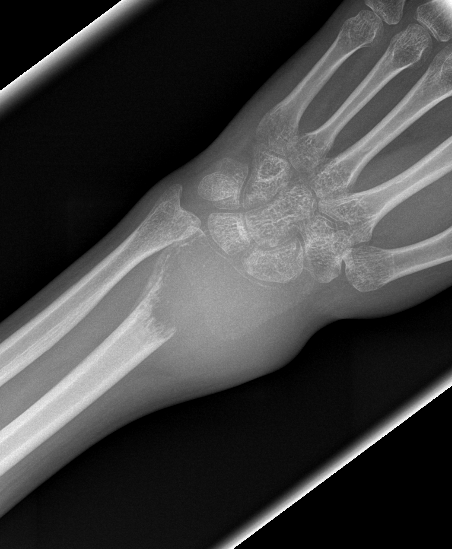

Distal Radius

Abuhejleh et al Eur J Orthop Traumatol Surg 2020

- 57 patients with GCT's of distal radius

- 29% (10/34) recurrence with intra-lesional treatement but no complications

- 4% (1/23) recurrence with wide resection / arthrodesis but 30% complication rate

- increased risk recurrence for Grade 3

- wide resection / arthrodesis should be reserved for grade 3

Koucheki et al Eur J Orthop Traumatol Surg 2023

- systematic review of 13 studies and 373 patients

- increased local recurrence with intralesional versus en-bloc resection

- especially Grade 3

- increased complications and poorer function with en-bloc resection

Distal radius GCT treated with en bloc resection and allograft reconstruction, followed by late wrist subluxation